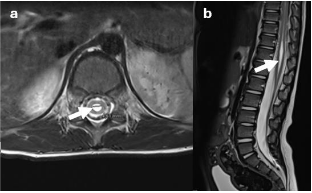

The data analyzed included gender, age at the time of surgery, and preoperative symptoms related to TCS. These symptoms encompassed motor function disturbances: degree of paresis, gait ataxia, ambulation ability, and results from neurophysiological tests such as somatosensory evoked potentials (SEPs) and, if performed, motor evoked potentials (MEPs), bladder function (urodynamic findings including bladder capacity, compliance, post-void residual volume, frequency of urination, catheterization frequency if applicable, incidence of urinary tract infections, and presence of urge or stress incontinence), bowel function, back pain, as well as the type and severity of foot or spinal deformities. Additionally, the presence of associated developmental disorders or genetic alterations. Each diagnosis was confirmed through lumbar magnetic resonance imaging (MRI) in conjunction with clinical and electrophysiological findings (exemplary illustration is provided in figure 1A and 1B).

Figure 1A. Syringomyelia in a T2-weighted lumbar MRI

T2-weighted axial (a) and sagittal (b) MR image demonstrating a pointed conus medullaris with associated syringomyelia (arrows) with a maximum diameter of 5mm. The underlying reason is a tight fatty filum (arrows), which can be seen in the corresponding T1-weighted axial (c) as well as sagittal (d) MR images.

Figure 1B. Tight fatty filum in a T1-weighted lumbar MRI